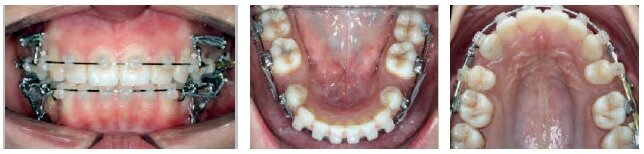

CASE NO 2

This patient, aged 15 years, was treated in 5 visits spread over 31 months.

These photos show the treatment stages and the intervals between appointments. A Damon System was used to treat this case of a Class III malocclusion, with incredible results observed in the teeth and facial features.